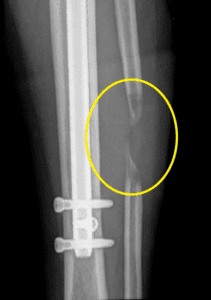

4 合并延迟或失败

任何延长手术都可能发生骨骼愈合缓慢或失败的情况。最好的治疗方法是预防。我们首先确定可能在手术前减缓愈合的因素:骨质疏松症、佝偻病、更年期、维生素 D 水平低、吸烟/电子烟(包括二手烟)、使用抗炎药、使用抗惊厥药物和其他药物使用。我们还推荐补充剂以帮助骨骼更快愈合(硅酸)。所有患者都服用维生素 D 补充剂,以防止延迟愈合。

自 2011 年我们开始使用 Precice 指甲以来,没有一名患者需要手术来治疗巩固延迟或失败。所有人都通过非手术方法成功治疗,包括唑烷酸输注、甲状旁腺激素 (维生素 D 和其他补充剂以及 Exogen 骨刺激剂。如果尽管采取了上述所有步骤,但仍出现延迟愈合,我们开始使用手风琴技术。使用 ERC 装置,骨骼每天压缩 1 毫米,每天分散注意力 1 毫米。这个循环每天重复几次。这会刺激骨骼愈合并避免手术的需要。

如果需要手术,我们知道如何通过手术使骨头愈合。当我们使用一些没有速率控制的旧植入钉(例如 ISKD)时,我们获得了这种经验。骨愈合失败的情况并不少见。因此,我们非常熟练地使用骨和骨髓移植来使骨骼愈合。虽然我们希望 Precice 或 STRYDE 指甲永远不需要它,但如果我们确实需要它作为后备,我们在根据需要管理这种并发症方面非常有经验。对于外科医生来说,不仅要知道如何进行手术,还要知道如何处理所有潜在的并发症,这一点至关重要。

患者在外部设施中延长后出现间歇愈合

该患者在外部设施中身材延长了厘米。完成延长手术几个月后,腓骨的间歇愈合很小。